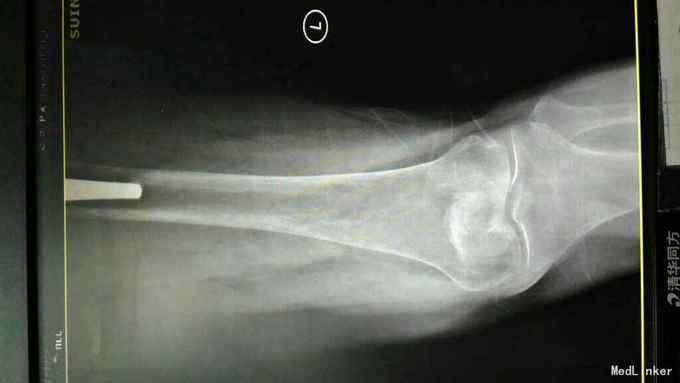

主诉:左髋关节置换术后疼痛活动受限3年 病史:3年前患者因左股骨颈骨折在当地县医院就诊,诊断明确后行全髋关节置换术,术前正常出院。出院后即感左髋关节疼痛不适,活动疼痛加重,休息缓解,疼痛位于腹股沟明显。反复于当地医院及成都等医院就诊,诊断不明确,考虑有金属过敏可能。4天前患者疼痛加重,活动进一步受限,无关节红肿,无肿胀,无畏寒发热,无其他关节疼痛。为进一步治疗收入我科。 患病以来。精神食欲可,体力下降。

查体:轮椅推入,左髋关节后外侧见10cm手术切口瘢痕,双侧腹股沟压痛,双侧大转子叩痛,双髋关节活动受限,4字实验(+),双下肢肌力3级。左乱关节屈曲90度,旋转不能。左下肢纵向叩痛(+)。 辅助检查:彩超示脂肪肝。x线腰椎骨质疏松,压缩性骨折。ESR 38,CRP 12。 影像学如下:

诊断:左髋关节置换术后假体松动; 右侧股骨头缺血坏死; 重度骨质疏松症 高血压病 压缩性骨折 治疗:左髋关节翻修术。(植骨、钛网骨水泥杯,骨水泥柄或翻修长柄MP(Link))